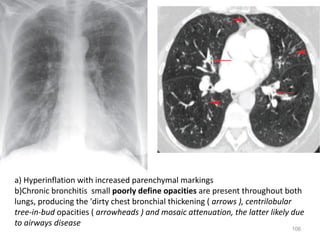

a) Hyperinflation with increased parenchymal markings

b)Chronic bronchitis small poorly define opacities are present throughout both

lungs, producing the 'dirty chest bronchial thickening ( arrows ), centrilobular

tree-in-bud opacities ( arrowheads ) and mosaic attenuation, the latter likely due

to airways disease